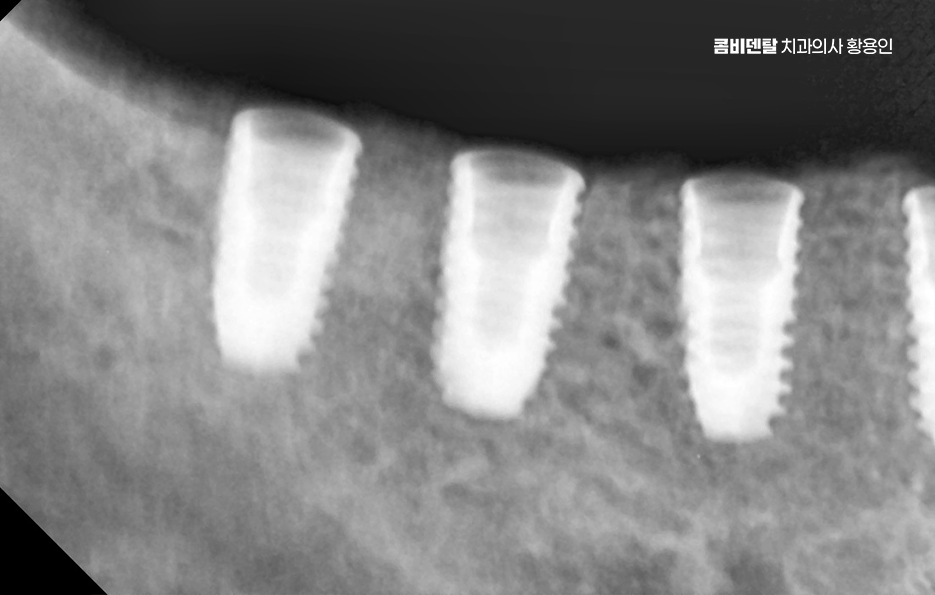

임플란트는 턱뼈 안에 임플란트의 고정체(인공치근)를 식립해서 치아를 대신하는 구조로 이 고정체가 제대로 자리를 잡고 버텨주려면 최소한의 잇몸뼈 높이와 넓이, 골질이 확보돼 있어야 안정성이 확보되는 거예요. 그런데 이 뼈가 부족한 상태에서 임플란트 뼈이식 안하면 그리고 억지로 임플란트를 심게 되면 어떤 일이 생기냐면, 첫째로 임플란트가 제대로 뼈와 붙지 못해서 탈락하거나 흔들릴 가능성이 높고 둘째로는 식립 부위 주변의 잇몸이 꺼지면서 심미적으로도 부자연스러운 결과를 낳을 수 있어요

잇몸뼈는 자연치아를 잃고 나면 시간이 지남에 따라 서서히 흡수되는데 특히 상실한 치아를 오랫동안 방치한 경우에는 뼈가 눈에 띄게 줄어드는 일이 흔하고, 치주염이나 염증이 반복된 경우에도 주변 골조직이 녹아내려 뼈의 두께와 높이가 부족해지게 되는데 이런 상태에서 임플란트 뼈이식 안하면 그리고 임플란트를 바로 심는다면, 뼈의 지지력이 부족하기 때문에 인공치근이 쉽게 움직이거나 주변에 염증이 생겨 골융합이 제대로 되지 않게 되고 결국엔 수개월 후에 탈락하거나 실패하게 되는 일이 생길 수 있는 거예요.

실제로 초기에는 잘 버티는 듯 보여도 시간이 지나면서 점점 임플란트 주변의 골이 소실되고, 결국엔 고정체가 노출되면서 통증, 염증, 보철물 탈락 같은 문제가 연쇄적으로 이어질 수 있어요